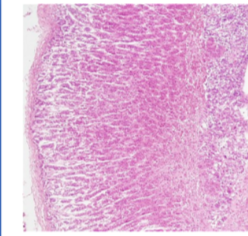

anterior pituitary